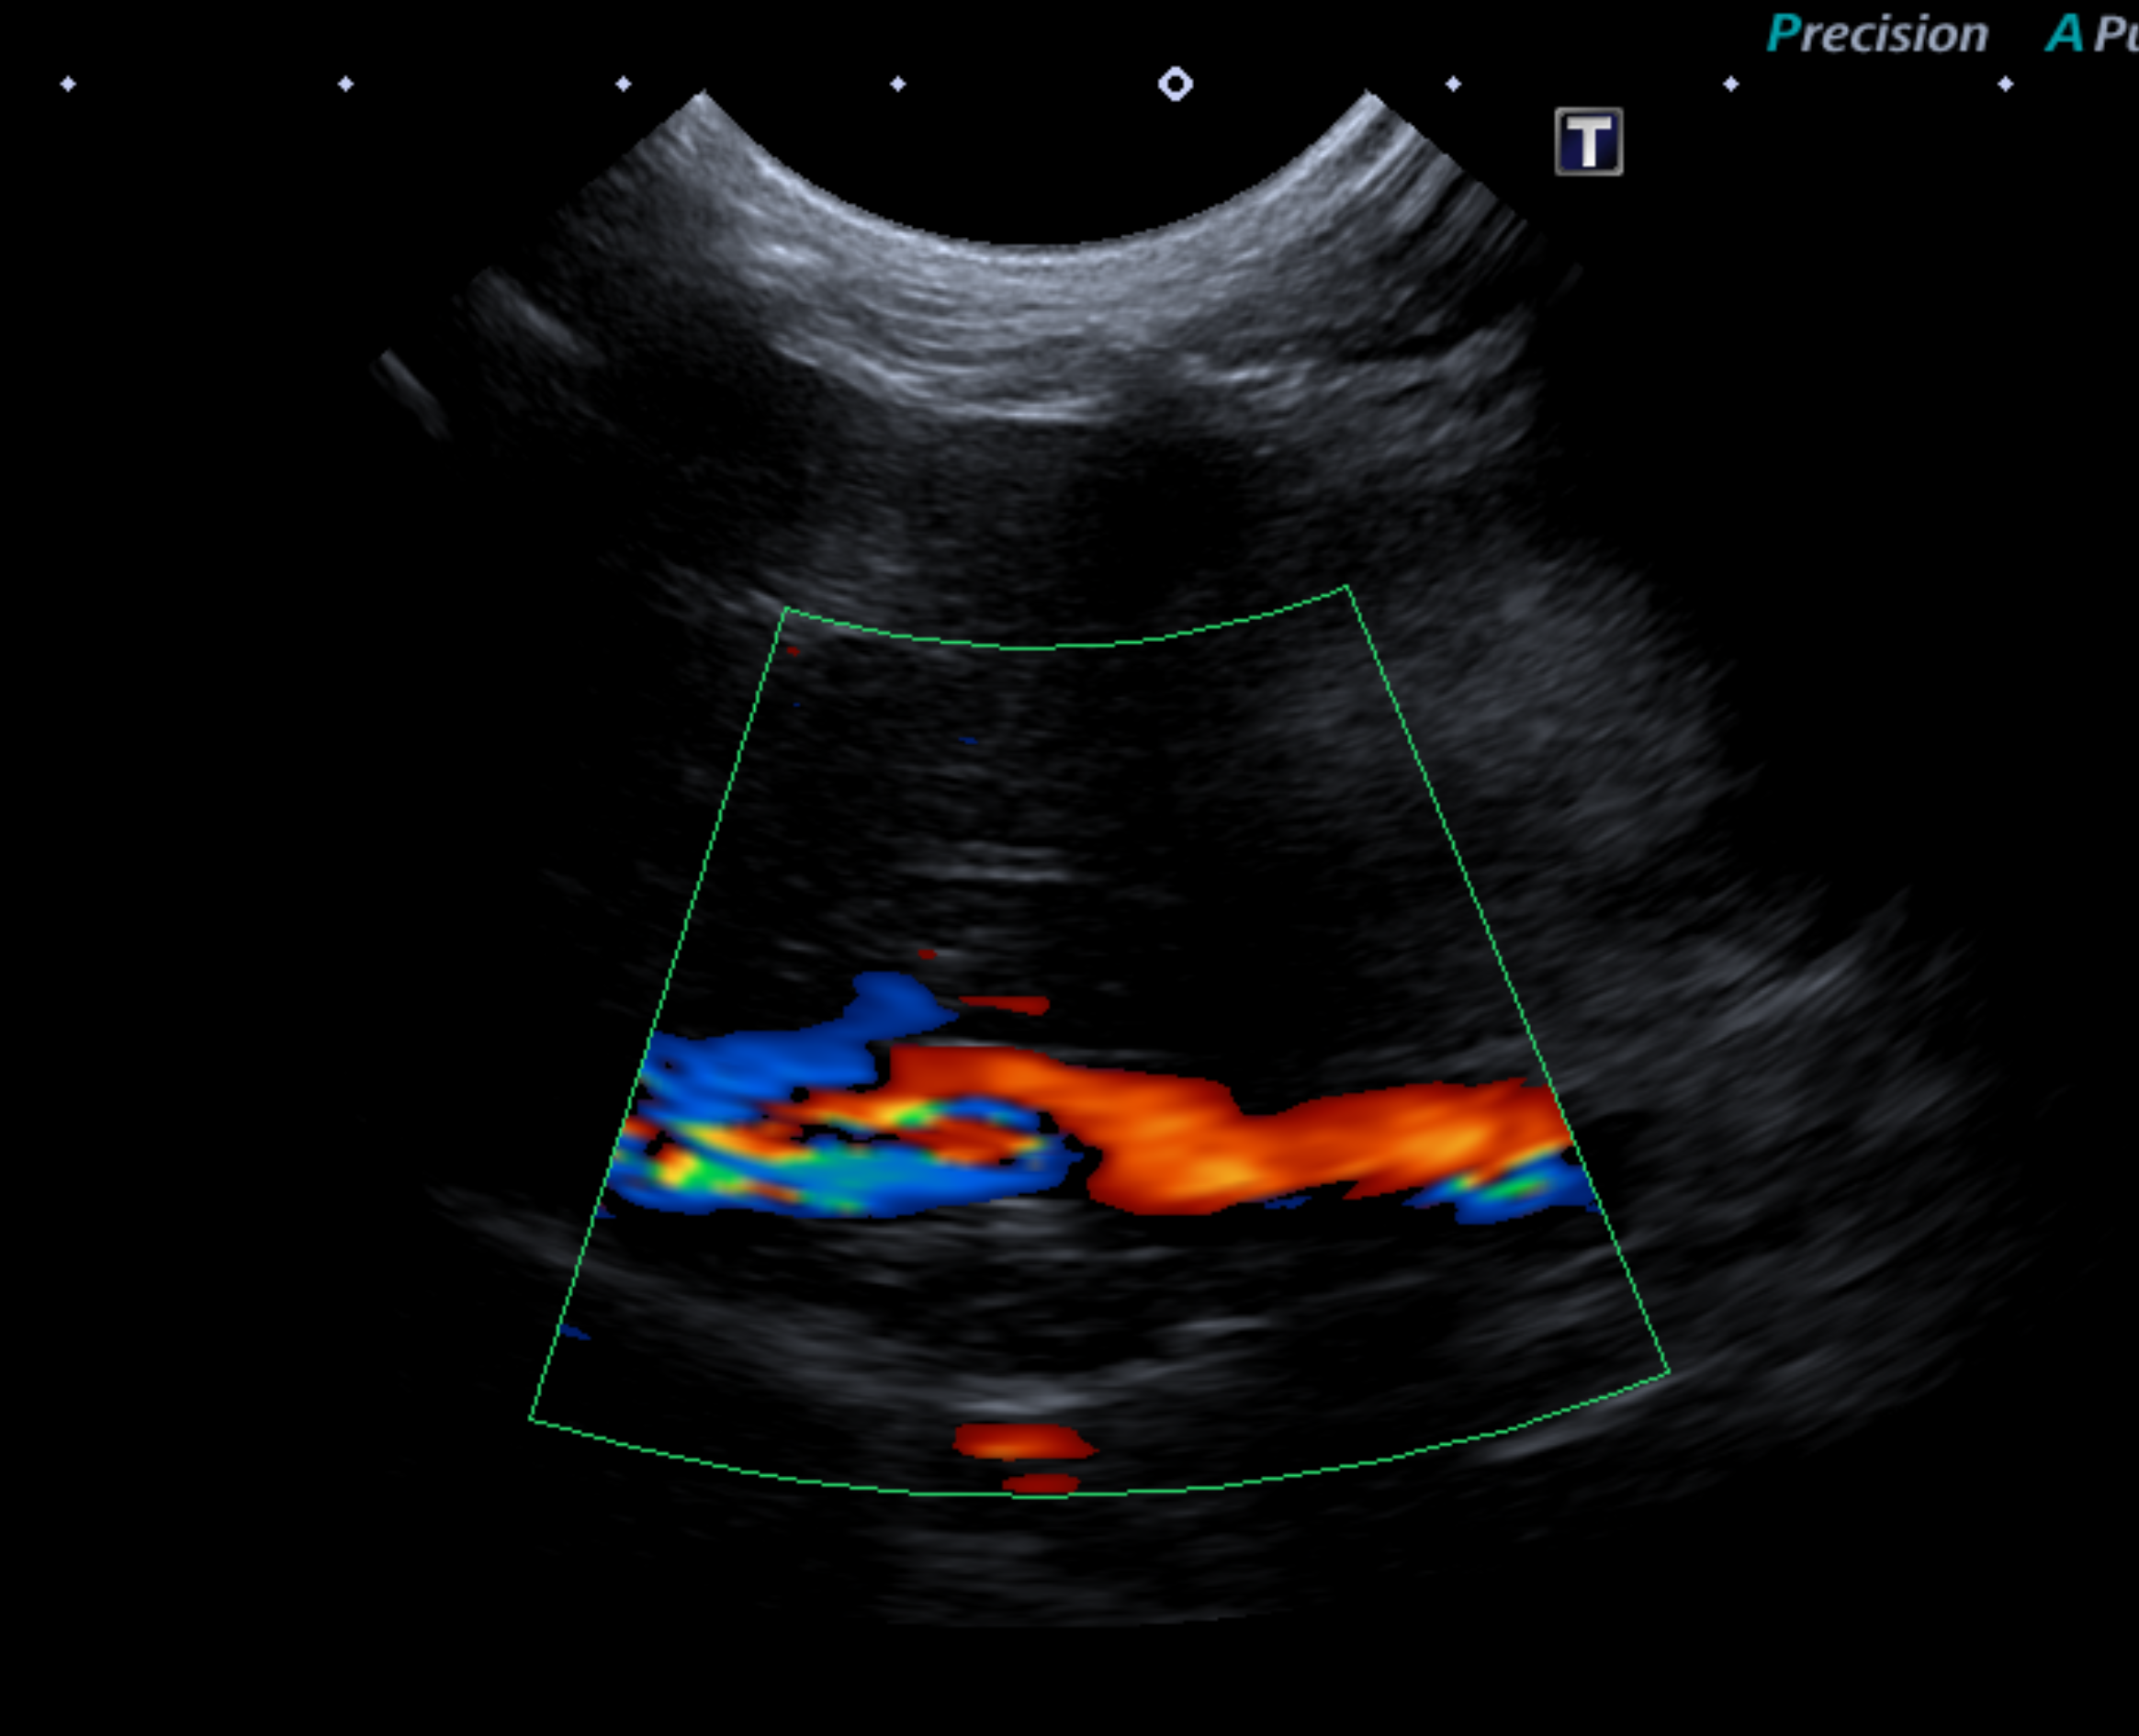

食前と食後のアンモニアとTBAの数値です。 食前、食後ともにTBAが高値であり超音波検査において後大動脈、後大静脈、門脈の他にもう1本異常な血管が確認され、血流の乱流も確認されました。

以上の検査より、門脈体循環シャントを疑いCT画像検査を行いました。